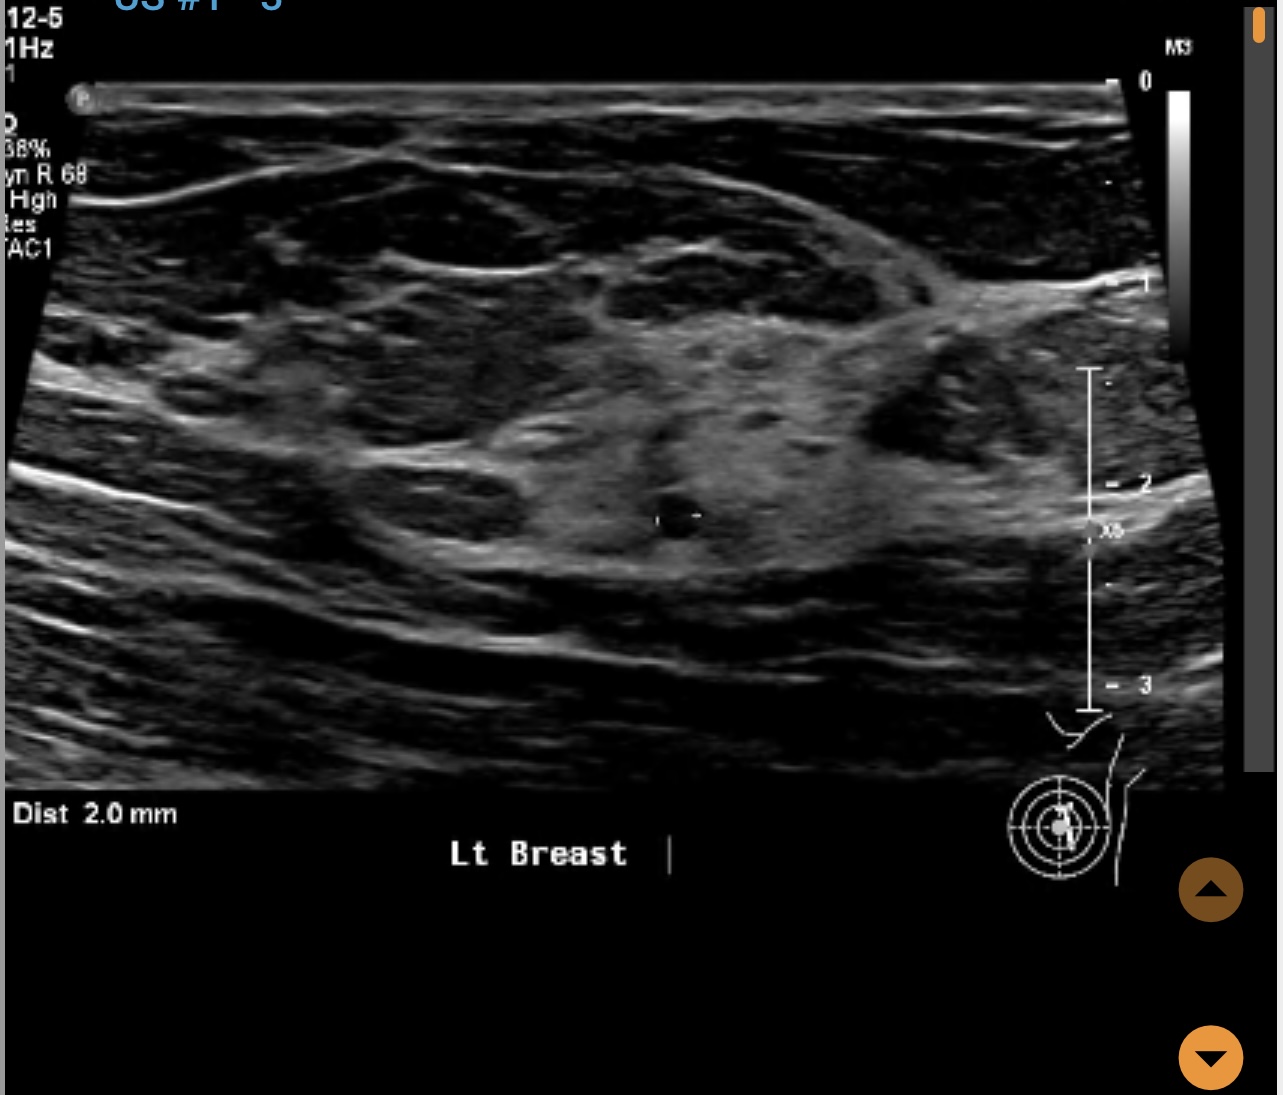

Left breast ultrasound report said no concerns. Symptoms - enlarged lymph nodes left breast, small cyst, changes in size and shape of left breast, dimples in lower left breast, pain in outer quadrant of left breast. Second opinion on ultrasound pics?